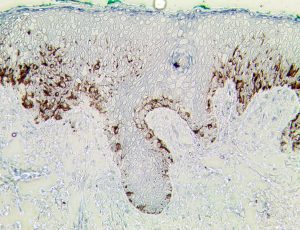

Bio SB has developed high affinity IVD monoclonal antibodies for fast immunohistochemistry (IHC) detection of melanoma, basal cell carcinoma (BCC), squamous cell carcinoma (SCC) and other Mohs surgery related conditions. Combined with our innovative IHC detection systems, we are opening the doors to a faster and more accurate immunohistochemistry applicable to Mohs surgery.

Bio SB has developed a fast, non-biotin monovalent Fab micropolymer IHC detection system for the detection of IVD antibodies for melanoma, BCC, SCC and other Mohs surgery related conditions. Our innovative IHC detection systems have opened the doors for a faster and accurate immunohistochemistry applicable to Mohs surgery.